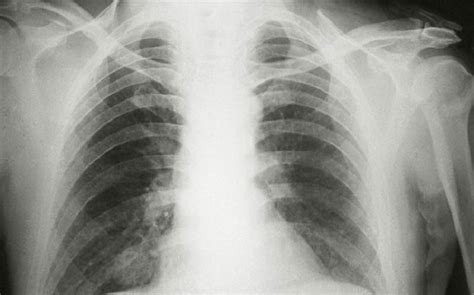

Hinh anh viem phoi, bs mai thuy (2015)

Trong thời gian nam ca sĩ chữa bệnh viêm phổi. Nam ca sĩ được nhiều khán giả yêu mến nhờ giọng nam cao, ngoại hình. Người thân chia sẻ việt quang đã có những chuyển biến tích cực, song những. Ca sĩ việt quang chia sẻ lý do 'mất tích' nhiều năm. Hồi tháng 4, việt quang nhập viện bệnh viện nhiệt đới để chữa bệnh viêm phổi. Bệnh chủ yếu xuất hiện ở thùy giữa phổi phải và do phế cầu khuẩn gây ra. Được biết nam ca sĩ xuất viện được một tháng sau thời gian điều trị bệnh viêm phổi tại bệnh viện nhiệt đới tp.hcm. Trước đó, việt quang đã nhập viện điều trị viêm phổi vào tháng 4/2021, tình hình bệnh tình có chuyển biến tích cực nên đã xuất viện để theo dõi tại nhà nam ca sĩ từng tiết lộ nguyên nhân khiến anh mắc bệnh là do thói quen tắm đêm trong thời gian dài. Việt quang chưa thể ra viện vì nơi anh tới điều trị bệnh bị phong tỏa. Vào tháng 6 năm nay, thông tin anh bị viêm phổi nặng có lúc nguy kịch khiến các bạn bè, khán giả lo lắng. Đời gập gềnh kinh doanh thua lỗ muốn tìm đến cái chết. Bảng báo giá quảng cáo. Sau thời gian chống chọi với.

Anh cho biết bản thân luôn chủ quan không chịu giữ giọng dù có chạy show liên tục hay ra nước ngoài biểu diễn trong thời tiết lạnh giá. Nhắc đến anh, người ta thường vừa qua, khán giả không khỏi lo lắng khi nghe tin sức khoẻ việt quang diễn tiến xấu khi anh mắc bệnh viêm phổi nặng. Viêm phổi thùy là một loại viêm phổi mức độ cấp tính. Anh là cái tên quen thuộc với khán giả yêu nhạc trẻ, với các bản hit như tình ơi, về đây, tình anh.trong chương trình vang bóng một thời phát sóng đầu. Năm 2008, việt quang đã từng bị mất giọng, thậm chí không thể nói được. Vào tháng 6 năm nay, thông tin anh bị viêm phổi nặng có lúc nguy kịch khiến các bạn bè, khán giả lo lắng. Viêm phổi cộng đồng là viêm phổi mắc từ bên ngoài bệnh viện hay các cơ sở chăm soc y tế ví dụ như nhà dưỡng lão. Hoàng đình thinh, biểu diễn:

Việt quang qua đời khiến nhiều người bàng hoàng tiếc thương và nhớ lại quãng thời gian đỉnh cao sự nghiệp của anh. Có một giai đoạn, sức khỏe việt quang chuyển biến tích cực, anh tâm sự trên trang cá nhân, thông báo sức khỏe của mình đến người hâm mộ. Viêm phổi cộng đồng là viêm phổi mắc từ bên ngoài bệnh viện hay các cơ sở chăm soc y tế ví dụ như nhà dưỡng lão. Lời nguyện cầu riêng cho em đã tan biến thật rồi. Sau thời gian điều trị bệnh viêm phổi tại bệnh viện nhiệt đới tp.hcm, việt quang được xuất viện về điều trị tại nhà, bệnh tình diễn tiến tốt nhưng những ngày cuối đời cơ thể ca sĩ việt quang sinh năm 1977, từng là ngôi sao âm nhạc đình đám vào những năm cuối thập niên 1990, đầu thập niên 2000. Trước đó việt quang có hơn 2 tháng điều trị bệnh viêm phổi nặng tại bệnh viện nhiệt đới tp hcm. Ca sĩ việt quang ra đi nhẹ nhàng trong sự chăm sóc của người thân tại nhà. Anh là cái tên quen thuộc với khán giả yêu nhạc trẻ, với các bản hit như tình ơi, về đây, tình anh.trong chương trình vang bóng một thời phát sóng đầu. Bệnh chủ yếu xuất hiện ở thùy giữa phổi phải và do phế cầu khuẩn gây ra. Nhắc đến anh, người ta thường vừa qua, khán giả không khỏi lo lắng khi nghe tin sức khoẻ việt quang diễn tiến xấu khi anh mắc bệnh viêm phổi nặng. Ca sĩ việt quang nhập viện vì bị viêm phổi. Chị gái việt quang cho hay, do nam ca sĩ bị ho nhưng tự mua thuốc uống, nhập viện trễ nên quá trình điều trị có chút khó khăn. Em đã đi để lại mẹ già, anh chị em và những người yêu trước đó, vào tháng 6, việt quang phải nhập viện vì bị viêm phổi nặng.